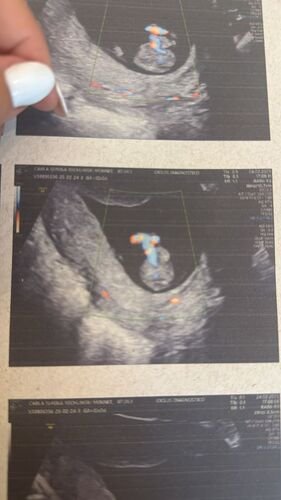

Recentemente, recebemos a notícia de que o Zay foi diagnosticado com gastrosquise, uma condição congênita rara em que parte do intestino e, às vezes, outros órgãos, se desenvolvem fora do abdômen por uma abertura na parede abdominal.

Essa condição exige cuidados médicos especializados e intervenções cirurgicas logo após o nascimento. Assim que o Zay nascer, ele vai precisar passar por uma cirurgia para reposicionar os órgãos dentro do abdômen e fechar a abertura. Esse processo é delicado e o tempo de recuperação pode variar, exigindo que ele fique internado na UTI Neonatal por semanas ou até meses.

Para aumentar as chances de sucesso do tratamento, o Zay precisa nascer até agosto, antes de completar as 38 semanas de gestação. Estamos nos preparando para oferecer a ele o melhor cuidado possível, mas os custos com exames frequentes, acompanhamento médico hospitalizado, cirurgias e a longa internação hospitalar são extremamente altos.